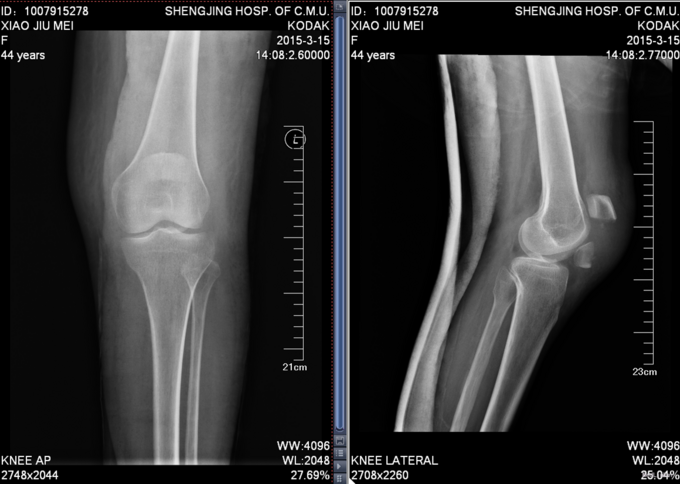

主诉:摔伤后左膝部疼痛肿胀活动受限4小时 患者及家属述患者于2015-3-14日9点40于自家不慎摔倒,导致左膝部疼痛肿胀活动受限,家人急送至沈阳市骨科医院,行DR检查示:左髌骨骨折。未行任何处理,现患者为求进一步诊治来我院,急诊以“左髌骨骨折”为主要诊断收入我科。患者自受伤以来,无发热,无呼吸困难,饮食睡眠正常,二便正常。

专科查体:患者平车入病房,。左膝部肿胀明显,压痛(+),活动受限。双下肢感觉正常 ,足趾活动可,足背动脉可触及。

诊断:左髌骨骨折 患者入院后见患肢肿胀明显,给予患肢石膏固定抬高位,冷敷,甘露醇消肿等对症治疗,带患肢出现褶皱试验阳性后,CSEA下行左髌骨骨折切口复位张力带内固定术,术后患者肿胀明显,给予,消肿,冷敷,患肢抬高等对症治疗。患者每天换药观察切口愈合情况,无红肿及渗出,待伤口12天后予以拆线治疗,予以出院,给予康复处方。